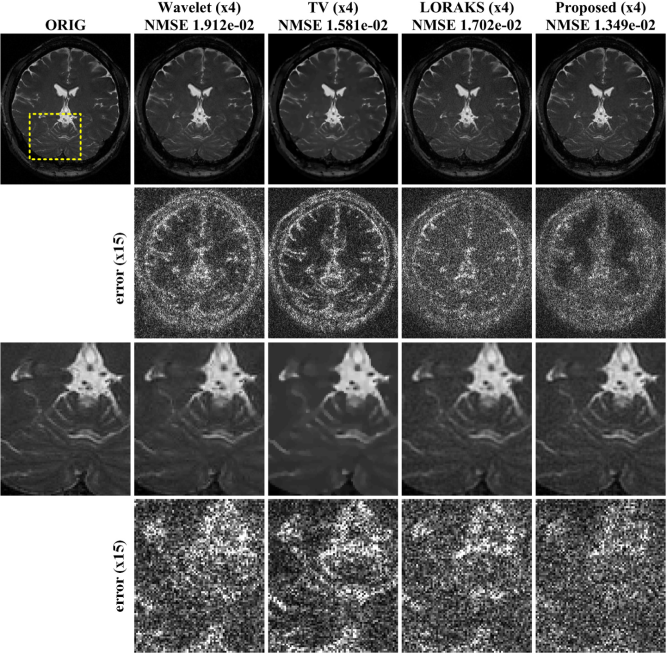

Reconstructed results from a single coil brain data are shown in Fig. 3 with the NMSE values. From the NMSE values, we observed that the performance ALOHA was quantitatively superior to the performance of -wavelet and TV based compressed sensing approach. The reconstruction results by ALOHA has less perceivable distortion compared to those of -wavelet and TV approaches. This can be easily observed from the difference images in the second and the fourth rows of Fig. 3. In the case of -wavelets and TV, structural distortion around the image edges was easily recognizable. In the last row of Fig. 3, the edges were reconstructed accurately by ALOHA. On the other hand, the contrast between grey matters and white matters in -wavelets and TV reconstruction were significantly distorted compared with that of ALOHA. The LORAKS reconstruction appeared better than that of -wavelets and TV reconstruction, but there were still remaining errors around the edges and the NMSE value was much higher than that of ALOHA.